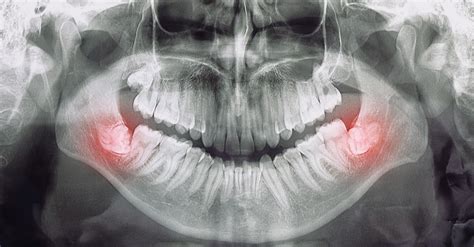

En el proceso en el que las muelas de juicio brotan es posible que se presenten otras complicaciones; tales como la periodontitis. A través de radiografías y TAC dental, un dentista puede saber si las muelas de juicio están causando algún problema, o si es probable que lo hagan en el futuro. En algunos pacientes se hace necesario cortar la muela en pedazos más pequeños para facilitar la extracción, luego se colocan unos puntos de sutura.

Diagnóstico y Planificación

Un examen clínico y radiológico es esencial para un diagnóstico preciso. El examen debe incluir:

- Examen general

- Examen regional

- Examen local

Las radiografías oclusales y panorámicas son cruciales para evaluar la posición y relación de los cordales con estructuras anatómicas vecinas.

Si es necesario hacer una radiografía oclusal para determinar la posición del cordal en relación con el seno maxilar o el conducto dentario inferior.